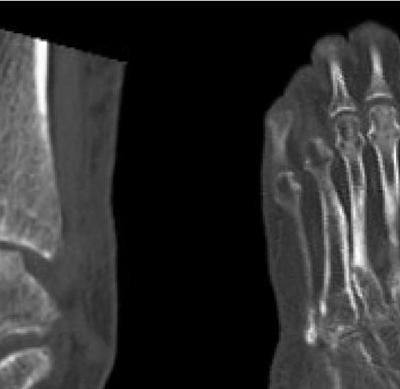

921 Charcot Neuroarthropathy of the Foot and Ankle in the Acute Setting: An Illustrative Case Report and Targeted Review

Kian Bagheri, Albert T. Anastasio, Alexandra Krez, Lauren Siewny, Samuel B. Adams

Duringthestudyperiodatotalof21participants comprising19residents(sixpostgraduateyear[PGY]1,